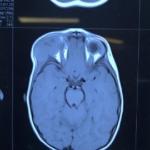

از دیرباز جراحی تومور های قاعده ی جمجمه یکی از مشکلات بزرگ در حیطه ی جراحی مغز و اعصاب بوده است. مهمترین مشکلی که سر راه جراحان همیشه قرار داشته است؛ رسیدن به تومور و جراحی کردن آن بدون آسیب دیدن به سایر نواحی مغز و نواحی حیاتی مغز بوده است.

با روش های متعددی توسط آندوسکوپ و میکروسکوپ می توان به قاعده ی جمجمه ی بیماران دسترسی پیدا کرد. بسیاری از اعمال جراحی های سخت امروزه امکان پذیر شده است. به عنوان مثال برای تومور هیپوفیز با استفاده از روش اندوسکوپی از راه سینوس های پارانازال و از راه داخل بینی دسترسی به تومور ورزکسیون آن به سادگی امکان پذیر شده است.

بسیاری از تومور های دیگر قاعده ی جمجمه مثل مننژیومایی که در قاعده ی جمجمه رشد می کند با روش های میکروسکوپی و حتی روش مینیمال انوازیو، از برش های کوچک قابل دسترسی است و بسیاری از این بیماران با این اعمال جراحی به بهبودی کامل می رسند.

امروزه با انواع روش کرانیوتومی یا برداشتن جمجمه و دسترسی به قاعده ی جمجمه و همینطور برداشتن تومور از ناحیه ی کف جمجمه بوسیله ی آندوسکوپ، به بسیاری از این تومور ها دسترسی امکان پذیر شده است.